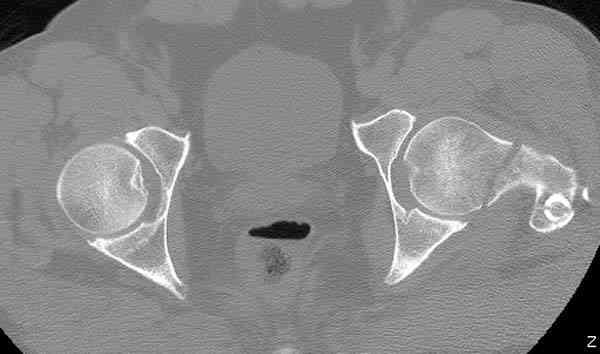

Здесь представлены снимки больного 65 лет, поступившего с диагнозом перелом

бедра после автоаварии.

На второй день (7) обнаружен пропущенный перелом,

сделаны Компьютерная Томограмма